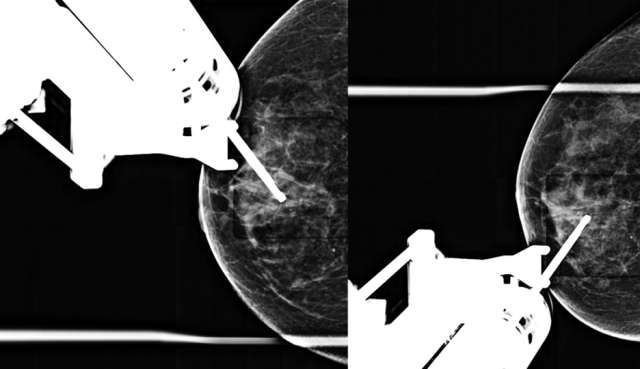

- Technologist takes a stereotactic pair of images (+/- 15 degrees) and radiologist confirms accurate trajectory (Figure 3).

Figure 3. Prefire stereotactic pair of CC images taken +/- 15 degrees.